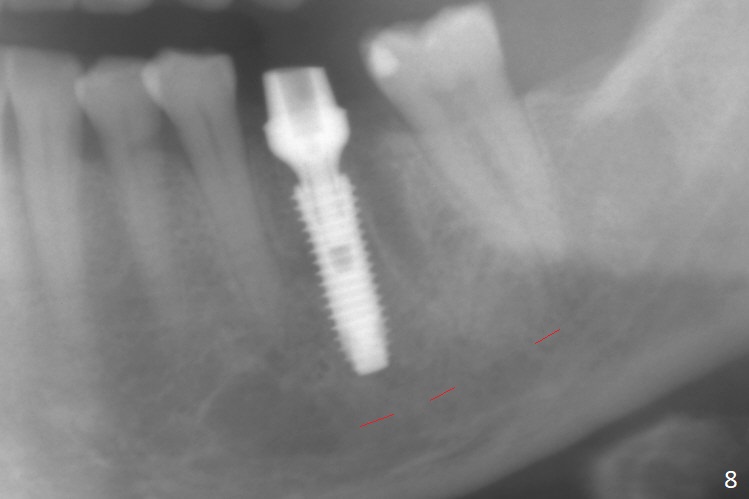

When the patient returns 9 months later, there is severe buccal gingival recession and abscess at #19 (Fig.1 *) with large mesial periradicular radiolucency (Fig.2 *).  The septum is thin and the buccal crest is low after extraction (Fig.3 * (mesial root vertical fracture)).  Osteotomy is initiated in the mesial socket immediately against the septum (Fig.4.5) with ~ 5 mm in the native bone.  Due to severe buccal plate resorption, a shorter implant is placed (Fig.6; 5x15 mm in stead of 18 mm).  There is at least 2 mm gap buccally for Vanilla Graft, which is also placed next to the implant and the neighboring root (Fig.7 *).  There is clearance from the Inferior Alveolar Canal (Fig.8 red dashed line).  Both the mesial and distal sockets heal 5.5 months postop (Fig.9), although the apical portion of the distal socket was not filled with allograft (Fig.7).  The implant was placed mesial.  The straight abutment (6.5x4(4) mm) (Fig.10) is changed to an angled one (5.5 x15 degrees 3 mm cuff (Fig.11)) before impression.  The implant is also placed buccally.  Therefore the implant position is far more important than its length.  The abutment is retightened 2.5 months post cementation, which is related to mesiobuccal placement of the implant (Fig.12).  An ideal trajectory is determined by drawing 2 horizontal lines (at crestal and apical levels: red lines in Fig.13), finding a central point of each line (vertical short line) and joining these 2 central points (Fig.14 pink line).  In fact the ideal osteotomy should have been established distal to the septum in this case.  Guided surgery may alleviate the issue.  The crown is not loose, but the patient feels that the implant tooth cannot sustain mastication.  In fact the screw is removed with hand driver (not wrench).  The abutment hex is rounded and worn.  A new 5.5x4(4) mm abutment is placed (without knowledge of previous use of an angled abutment) with mesial reduction to reduce undercut and buccodistal margin lowered to reduce gingival embrasure. It is that the straight abutment could decrease the chance of screw loosening.  Otherwise the implant has to be removed for better trajectory.